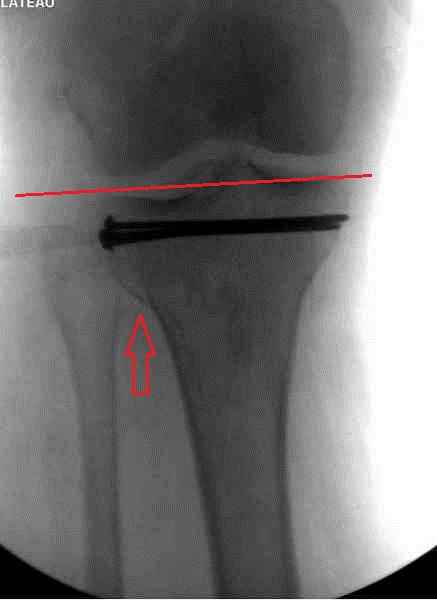

Как всегда прекрасная презентация. Совершенно согласен с необходимостью сохранять мениск и вообще согласен со всем, кроме одного. Фиксация должна проводиться после правильно выполненной репозиции. Главная цель репозиции - это восстановить высоту наружного мыщелка. В норме наружный мыщелок выше внутреннего на 4-5 мм на снимке в переднее заднем направлении АР.

Необходимость репозиции возникает при снижении высоты от 3 до 5 мм по разным источникам. По моему опыту 4 мм. Если не восстановить высоту мыщелка возникает вальгизация коленного сустава с относительным расслаблением передней крестообразной связки. При этом развивается нестабильность коленного сустава из-за недостаточности ПКС.

На представленном после операционном снимке нет репозиции, на что указывает низкое положение тибиального плато и перекрытие кортикальных пластинок в метафизарной части - указано стрелкой. Обычно чрескожную фиксацию я применяю

при переломе без депрессии отломка, или если после СТ понятно, что можно сделать закрытую репозицию, то шуруп с шайбой можно установить прямо в угол, что предотвращает скольжение отломка.